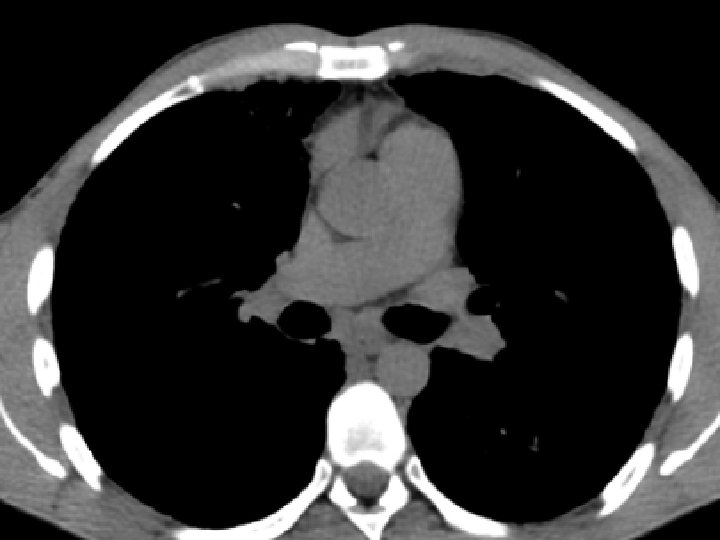

High-resolution CT scan

Subpleural, basal predominance Reticular abnormality Honeycombing with traction bronchiectasis UIPUIP Pattern

Subpleural, basal predominance Reticular abnormality Honeycombing with traction bronchiectasis Profuse micronodules UIPUIP Pattern Inconsistent with UIP Pattern